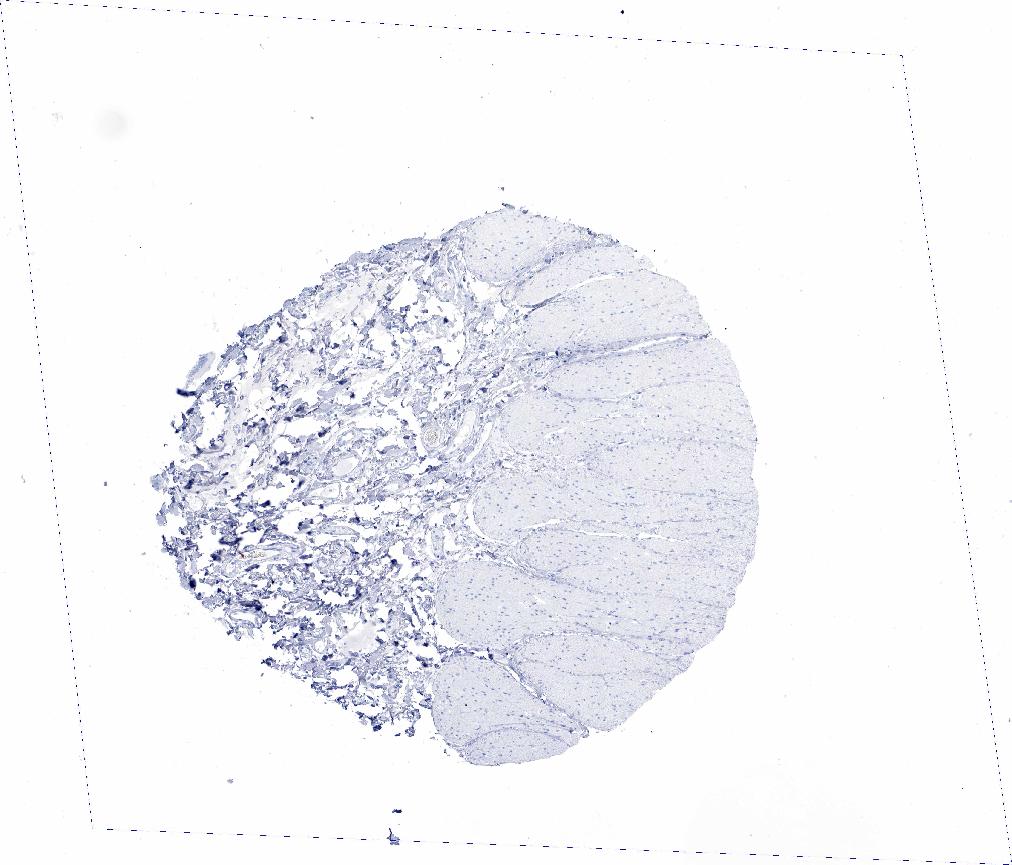

ADIPOSE TISSUE - Antibody stainingi

Antibody staining in the annotated cell types in the current human tissue is reported as not detected, low, medium, or high, based on conventional immunohistochemistry profiling in selected tissues. This score is based on the combination of the staining intensity and fraction of stained cells.

Each image is clickable and will lead to virtual microscopy that enables deeper exploration of all samples and also displays staining intensity scores, fraction scores and subcellular localization as well as patient and tissue information for each sample.

Antibody HPA019141Antibody CAB000047

Adipocytes Not detectedNot detected